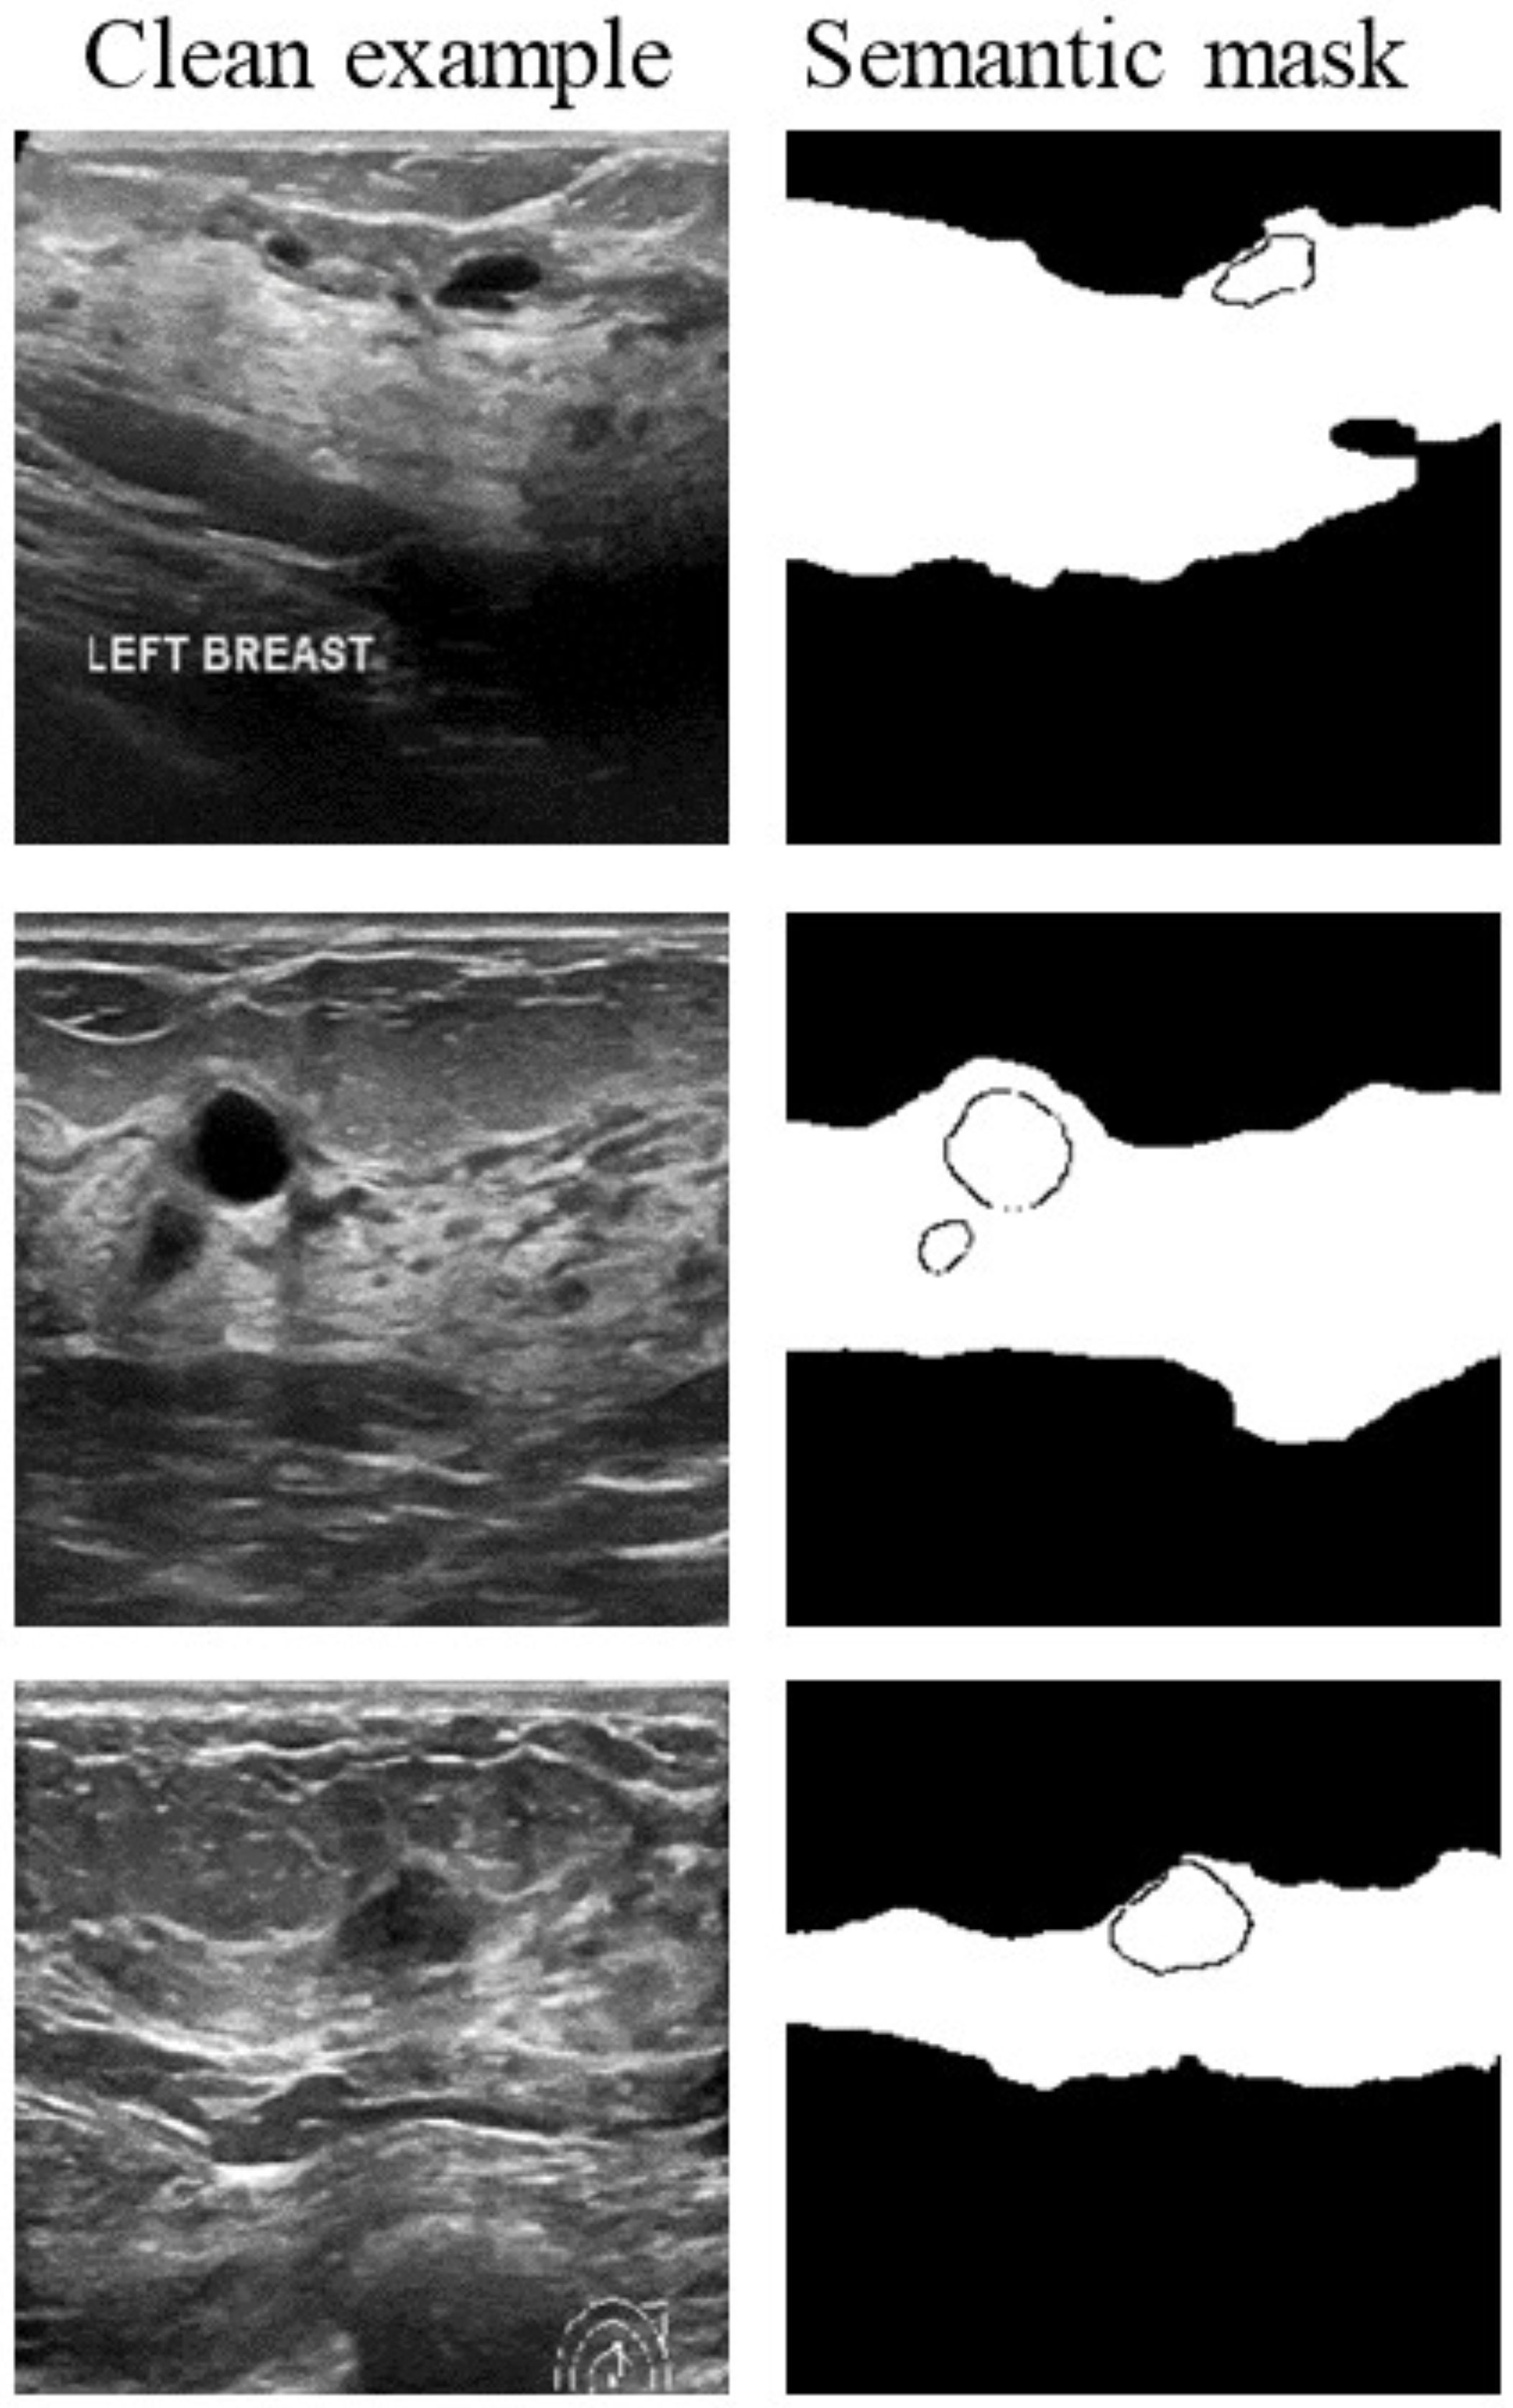

Inspired by the regional masking approach [34] and the nature of BUS images, this work proposes a semantic-aware search approach to reduce the dimensionality of search directions. In Algorithm 2, the semantic mask M is generated by using A2DMN [35] and has non-zero values for tumor and mammary regions (Figure 3), and Q is the query budget. In lines 3–5, the vector of the search direction is split into blocks, and all pixels in a block change directions together. Lines 10–11 adaptively increase the number of blocks to crop when fine-splitting () is applied. Line 14 limits the search to blocks in the union of the semantic mask M and cropping mask, which lets the search focus on regions of interest. The cropping mask trims blocks at the top and bottom of an image. Lines 15–17 attempt to find an adversary along the current direction; if this fails, the current direction is skipped. Lines 18–19 apply the proposed AdaptBS algorithm to get the best adversary along the current direction and update the best search direction () and best distance.

Figure 3.

BUS images (left column) and their respective semantic masks for the mammary and tumor regions (right column).

In Figure 4, the cropping mask can be considered as a pruned branch to remove unnecessary parts of the search space, compared with RayS. The union of semantic masks and cropping masks skips checking a region that does not contain crucial features.